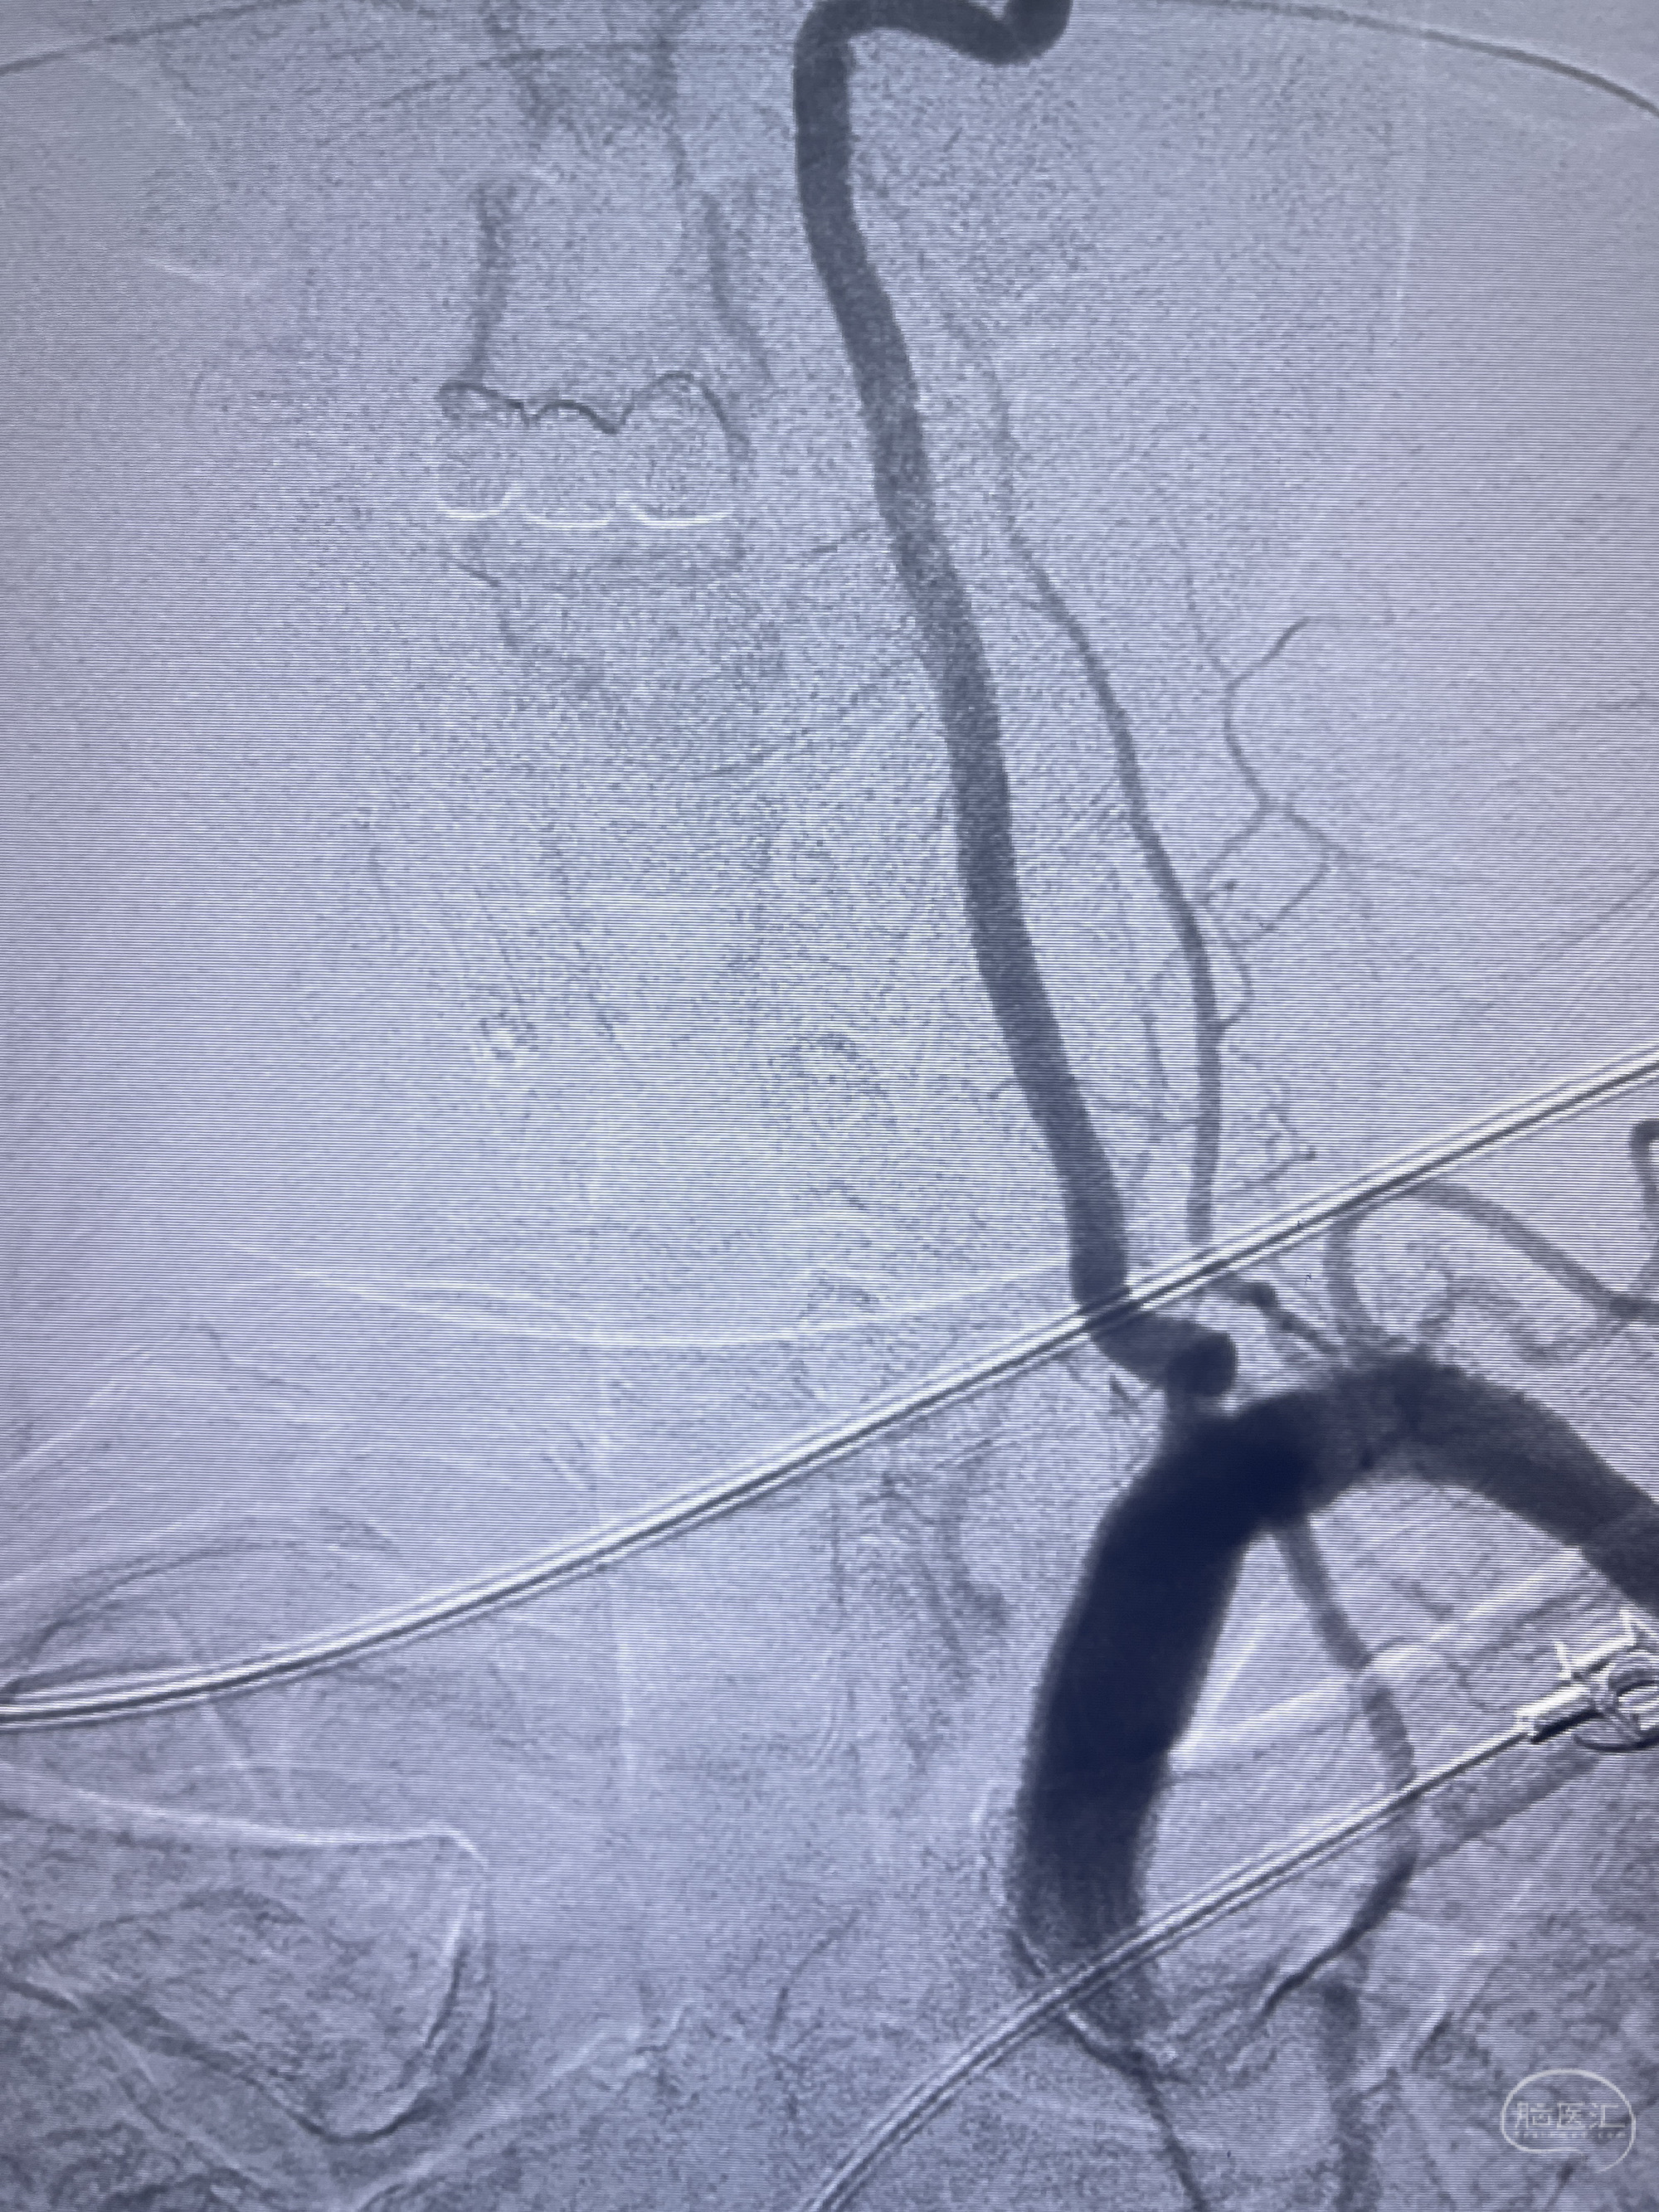

202.04.28脑血管造影:右侧大脑后动脉远段闭塞,右侧椎动脉V4段可见“囊状造影剂填充影”,大小7.64*7.65mm,可见PICA由动脉瘤发出;